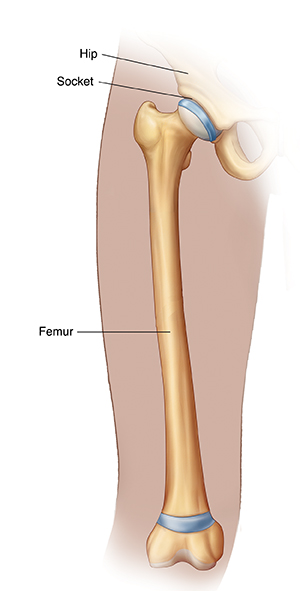

A femoral osteotomy is a type of surgery. Your child may need it if they have a problem with their hip joint and femur. The femur is the thighbone that joins the pelvis to the knee. During this surgery, a small part of the femur is cut out so the bone fits better into the hip socket.

This surgery is most often done in children who are born with a hip abnormality, such as hip dislocation (developmental dysplasia of the hip). Your child’s health care provider may advise it when the top of the femur does not fit well into the hip socket. Your child’s pelvic and femur bones may not work together the right way. The femur may be angled too far forward or backward. Your child may walk with inward- or outward-facing toes.

The surgeon puts the femur in the right place. If needed, they turn it so the top part of it fits as it should into the hip socket.

The surgeon attaches a plate with screws or pins to the top of the femur. The plate helps align the femur in the hip socket and keeps the bone in place as it heals.